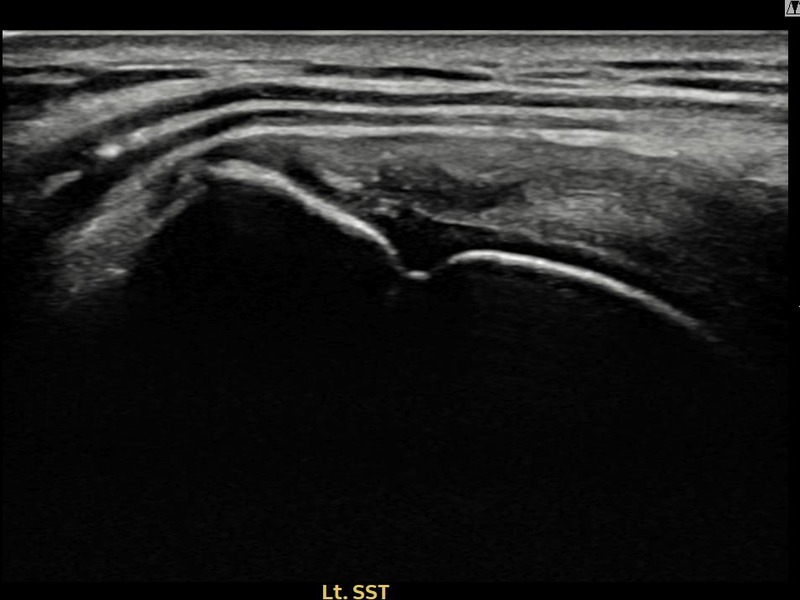

서ㅇㅇ님 · 좌측 극상근건 관절면측 부분파열

좌측 어깨 통증으로 팔을 올리기 불편하여 내원하셨습니다. 초음파 검사에서 관절면측 극상근건 부분파열이 확인되었으며, 어깨인대 축소봉합술 후 파열 부위 연속성이 회복되었습니다.

서ㅇㅇ님 · 좌측 극상근건 부착부 부분파열

좌측 어깨 부착부 통증과 야간 통증으로 수면 장애가 있어 내원하셨습니다. 초음파 검사에서 극상근건 부착부 부분파열이 확인되었으며, 어깨인대 축소봉합술 후 부착부 힘줄이 구조적으로 회복되었습니다.